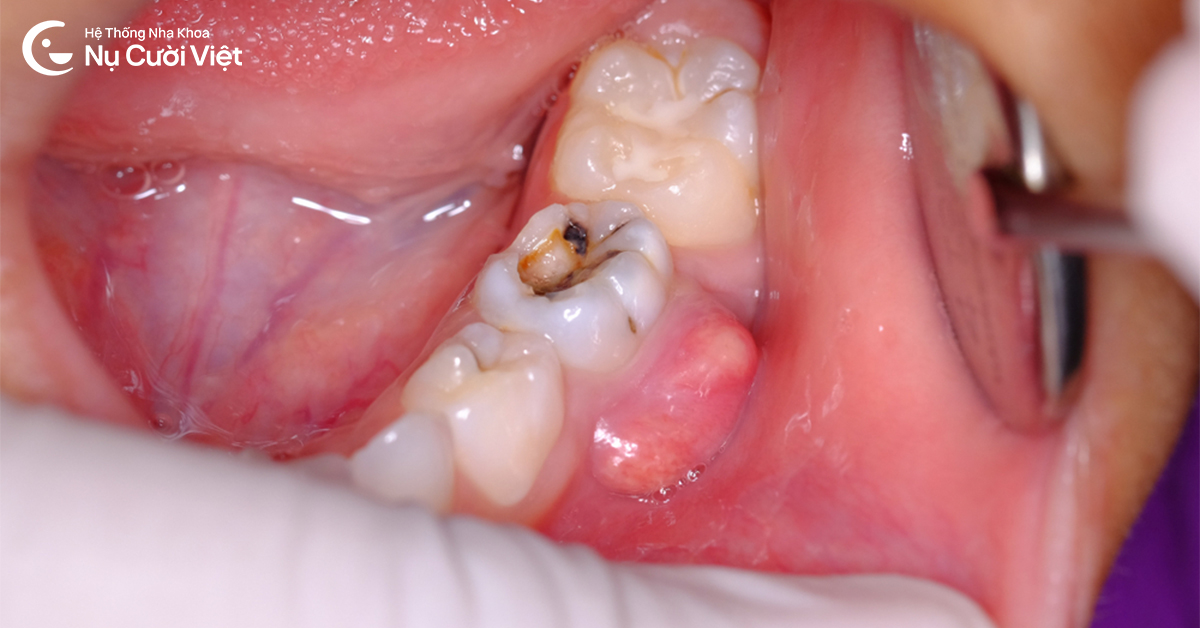

Sâu răng lâu ngày không được điều trị khiến tủy răng nhiễm trùng, gây sưng nướu răng có mủ

Áp xe răng và sâu răng nặng: Vi khuẩn tấn công vào tủy răng tạo ra các túi mủ ở vùng chóp chân răng, khiến nướu sưng to, đau nhức dữ dội và có thể gây sưng cả vùng má.